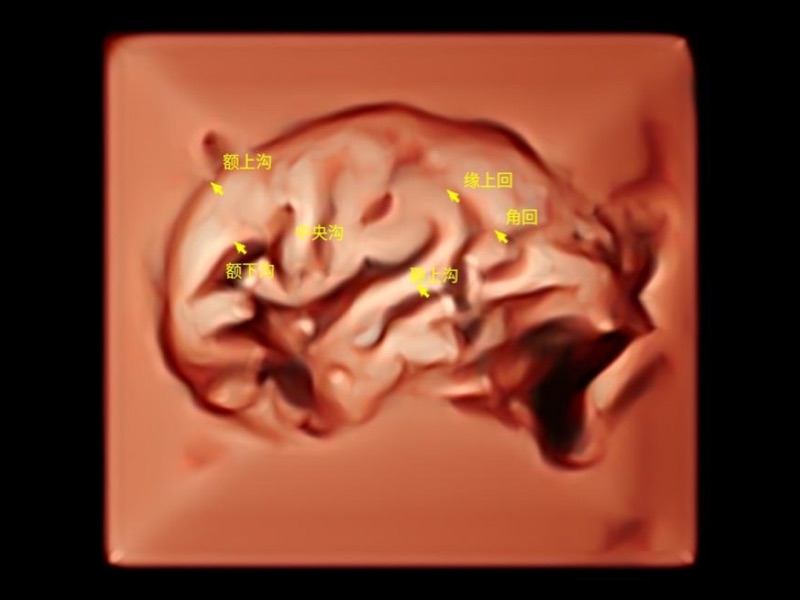

作为开立医疗全新打造的超高端旗舰超声产品,从探头抬起唤醒开启扫查到多维探头发射接收,通过先进的场成像发射、自适应聚合重建等技术,基于RF Data原始射频数据在图像生成、高端功能等方面实现突破,为妇产科、儿科提供全方位临床解决方案。

独有场成像发射技术

自适应聚合重建技术